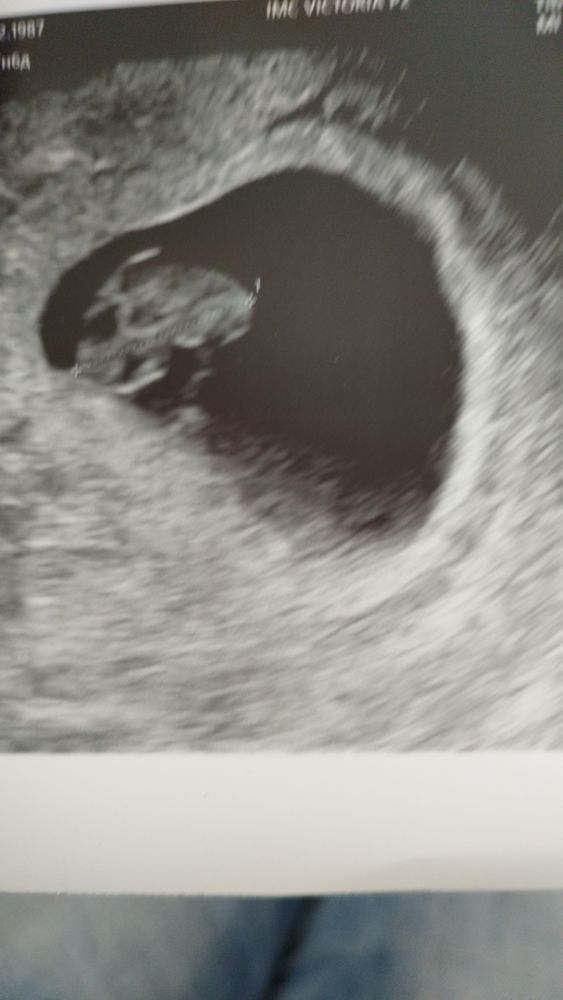

Первое УЗИ

Я БЕРЕМЕННА !

Нам 7 недель и 6 дней счастью нет предела услышала сердечко аж прослезилась))) Врач сказала что все как в аптеке ребенок развивается согласно своему возрасту ...наш рост уже 16мм. 22.05 записалась к врачу будем вставать на учет)))